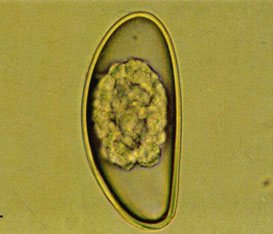

缩小膜壳绦虫虫卵(40×)

在分类学上隶属于扁形动物门、绦虫纲、圆叶目、膜壳科、膜壳属,常寄生于大、小鼠和仓鼠的小肠。属于人畜共患寄生虫,但人感染此绦虫的情况较少见。缩小膜壳绦虫的生活史必须有中间宿主参加才能完成,虫卵随终末宿主的粪便排至体外,中间宿主摄入虫卵,在体内发育为具有尾巴样构造的似囊尾蚴,终末宿主摄入被感染的中间宿主而被感染,经12-13天在终末宿主肠道内发育为成虫。中间宿主除蚤类外,还有甲虫、蟑螂及鳞翅目等多种昆虫,其中面粉甲虫和鼠蚤是最常见的中间宿主;终宿主为鼠或其他啮齿类动物,偶尔寄生于人。虫卵呈圆形,直径大小为60-65um,内含六钩蚴。